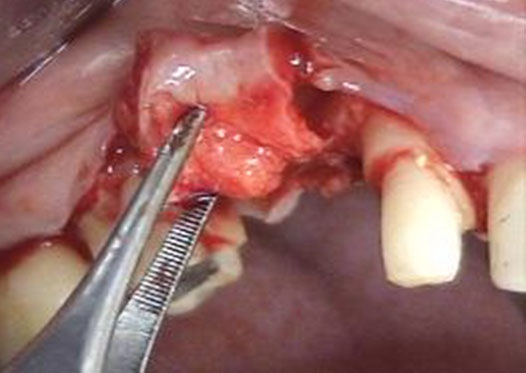

Se le aumentó a la paciente el reborde alveolar por medio de la técnica de rollo modificada, pero sin incisiones verticales ni en vestibular o palatino. El procedimiento quirúrgico consistió en incisiones intracreviculares en los dientes 16 y 13, una incisión paracrestal palatina superficial desde mesial del 16 hasta distal del 13. A partir de dicha incisión se levantó la tapa epitelial palatina y se realizaron incisiones verticales mesial y distal y horizontal apical internas del tejido conectivo, el cual se elevó y enrolló en vestibular, donde previamente se realizó un colgajo mucoso (figura 2). El pedículo se enrolló hacia vestibular y se aseguró con puntos de sutura a cada lado. Finalmente, se suturó la tapa epitelial palatina. El diente provisional o temporal se recortó en la parte cervical para evitar el contacto con el tejido blando y se entregaron instrucciones posquirúrgicas por escrito a la paciente. Se le medicó con nimesulida de 100 mg, una tableta cada 12 h durante 3 días; azitromicina de 500 mg, una tableta diaria durante 3 días; y enjuagues con clorhexidina 2 veces al día por una semana. La paciente salió sin dificultades del consultorio.